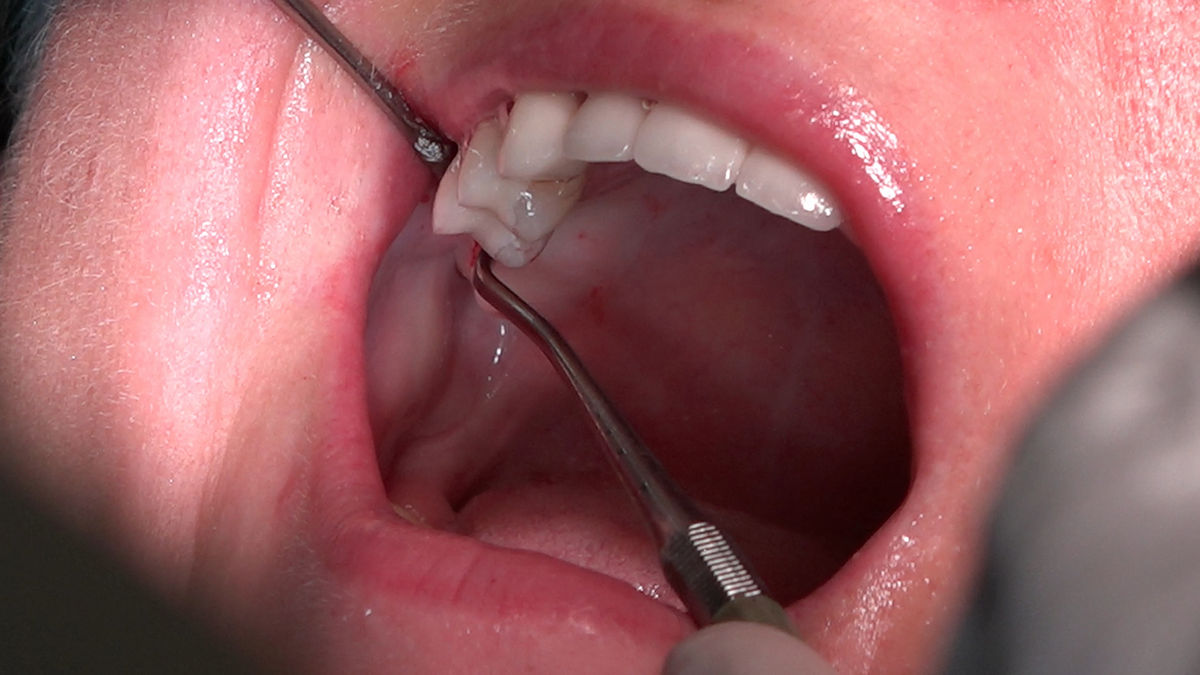

Chirurgia implantologiczna to temat wiodący 5 Sesji X Sezonu Practiculum Implantologii, która się odbyła 23-24 października 2020 roku. Bierze w nim udział 16 adeptów implantologii stomatologicznej. Zabiegi z udziałem Pacjentów jak zwykle poprzedziło omówienie i planowanie, tym bardziej, że zgodnie z planem wykonana została implantacja z wykorzystaniem szablonu chirurgicznego, który przygotowało laboratorium dentystyczne Wiligała Lab. Kursanci wykonywali szereg zabiegów implantologicznych i chirurgicznych oraz regeneracyjnych z zastosowaniem PRF, w tym sinus lift. Przeprowadzali je pod kierunkiem Lidera Umiejętności Implantologicznych dr n.med. Violetty Szycik, która wysoko oceniła wykonanie zabiegów.